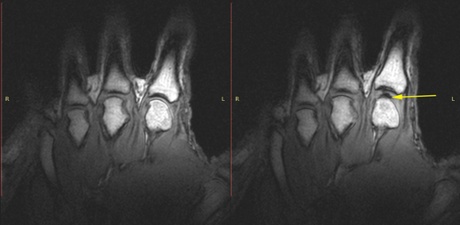

Images of the knuckles before (left) and after cracking (right).

Images of the knuckles before (left) and after cracking (right). Photograph: University of Alberta

Writing in the journal, Plos One, Kawchuk describes how every crack occurred as the joints suddenly separated, and a gas-filled pocket appeared in the synovial fluid that lubricates the joint. The bubble comes from gas that comes out of the fluid as the pressure in it drops, just as bubbles appear in freshly opened bottles of fizzy drinks. “If you’ve ever washed up glass plates, you’ll know they can be hard to separate when they are wet. The film of water between them creates a tension that needs to be overcome. It’s similar with joints. When you pull on them, they resist at first, and then suddenly give way,” said Kawchuck.